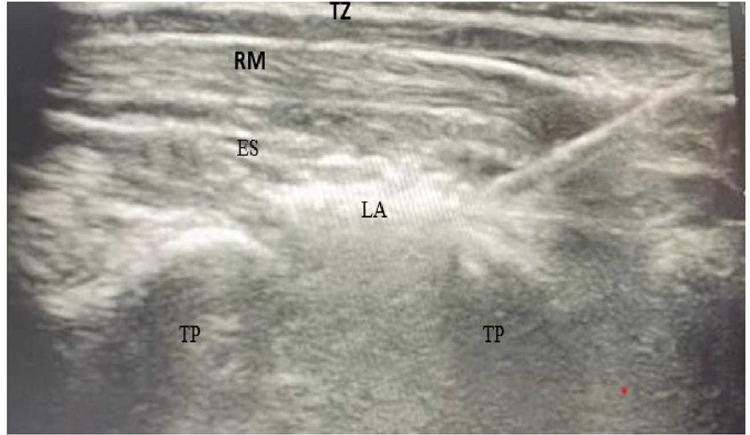

Sixty children with cancer ASA I or II and undergoing open radical nephrectomy between the ages of two and seven participated in this prospective, randomized, controlled, and open label study. The cases were divided into two equal groups (E and T groups); Group E received ipsilateral continuous ultrasound-guided ESPB at T (thoracic vertebrae), with a bolus of 0.4 mL/kg bupivacaine 0.25%. Immediately postoperatively, Group E (ESPB group) received continuous ESPB with a PCA (patient controlled analgesia) pump at a rate of 0.2 mL/kg/hour bupivacaine 0.125%. Group T (Tramadol group), Tramadol hydrochloride was administered intravenously at a dose of 2 mg/kg/8hour, which could be increased to 2 mg/kg/6hours. Then, we followed up on patients' total analgesic consumption for 48 hours following surgery, as well as the time it took for them to request rescue analgesic, their FLACC and sedation scores, and their hemodynamics and side effects immediately following surgery as well as at 2, 4, 6, 8, 12, 18, 24, 36, and 48 hours.

60例年龄在2至7岁、ASA I或II级且接受开放性根治性肾切除术的癌症患儿参与了这项前瞻性、随机、对照、开放标签研究。病例被分为两组(E组和T组),每组各30例。E组在T(胸椎)水平接受同侧超声引导下的连续性ESPB,给予0.4 mL/kg的0.25%布比卡因推注。术后即刻,E组(ESPB组)通过患者自控镇痛(PCA)泵以0.2 mL/kg/小时的速率给予0.125%布比卡因进行连续性ESPB。T组(曲马多组)静脉注射盐酸曲马多,剂量为2 mg/kg/8小时,可增加至2 mg/kg/6小时。然后,我们对患者术后48小时内的总镇痛药物消耗量、请求使用补救性镇痛药物的时间、面部表情、腿活动、活动、哭闹、安慰(FLACC)评分和镇静评分,以及术后即刻、术后2、4、6、8、12、18、24、36和48小时的血流动力学和副作用进行了随访。